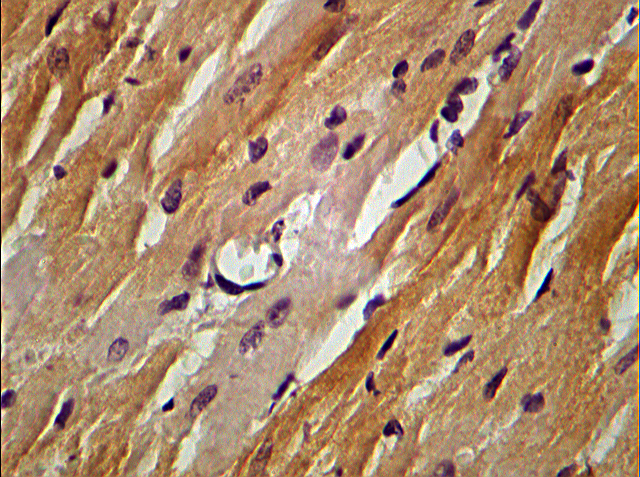

|  | 1. Рис. 2 Фрагмент миокарда ЛЖ крысы на 28 сут после моделирования ЭСН. Окраска: иммуноцитохимическая пероксидазная реакция для выявления ТИМП-1. Ув. об. 40, ок. 10 | |

| Тема | Фрагмент миокарда ЛЖ крысы | |

| Тип | Результаты исследования | |

Результаты. У ОЭ крыс на 14 сут ЭСН выявлены отчетливо выраженный гетероморфизм сократительных кардиомиоцитов (КМЦ) с признаками гипертрофии и дистрофии; увеличение объемной плотности (ОП) стромы, реорганизация внеклеточного матрикса (ВМ) (экспрессия металлопротеиназ-2,9 (ММП-2,9) и тканевого ингибитора металлопротеиназ-1 (ТИМП-1), КМЦ с явлениями апоптоза. После моделирования ЭСН на 28 сут в миокарде происходило дальнейшее нарастание количества КМЦ с существенно измененными морфологическими и тинкториальными свойствами, деградация компонентов ВМ миокарда. У крыс, получавших 14 сут дроспиренон, независимо от дозы, отмечался регресс патологических изменений, происходило уменьшение степени гипертрофии КМЦ и их ядер, снижение числа КМЦ с признаками апоптоза, стабилизация компонентов ВМ миокарда.